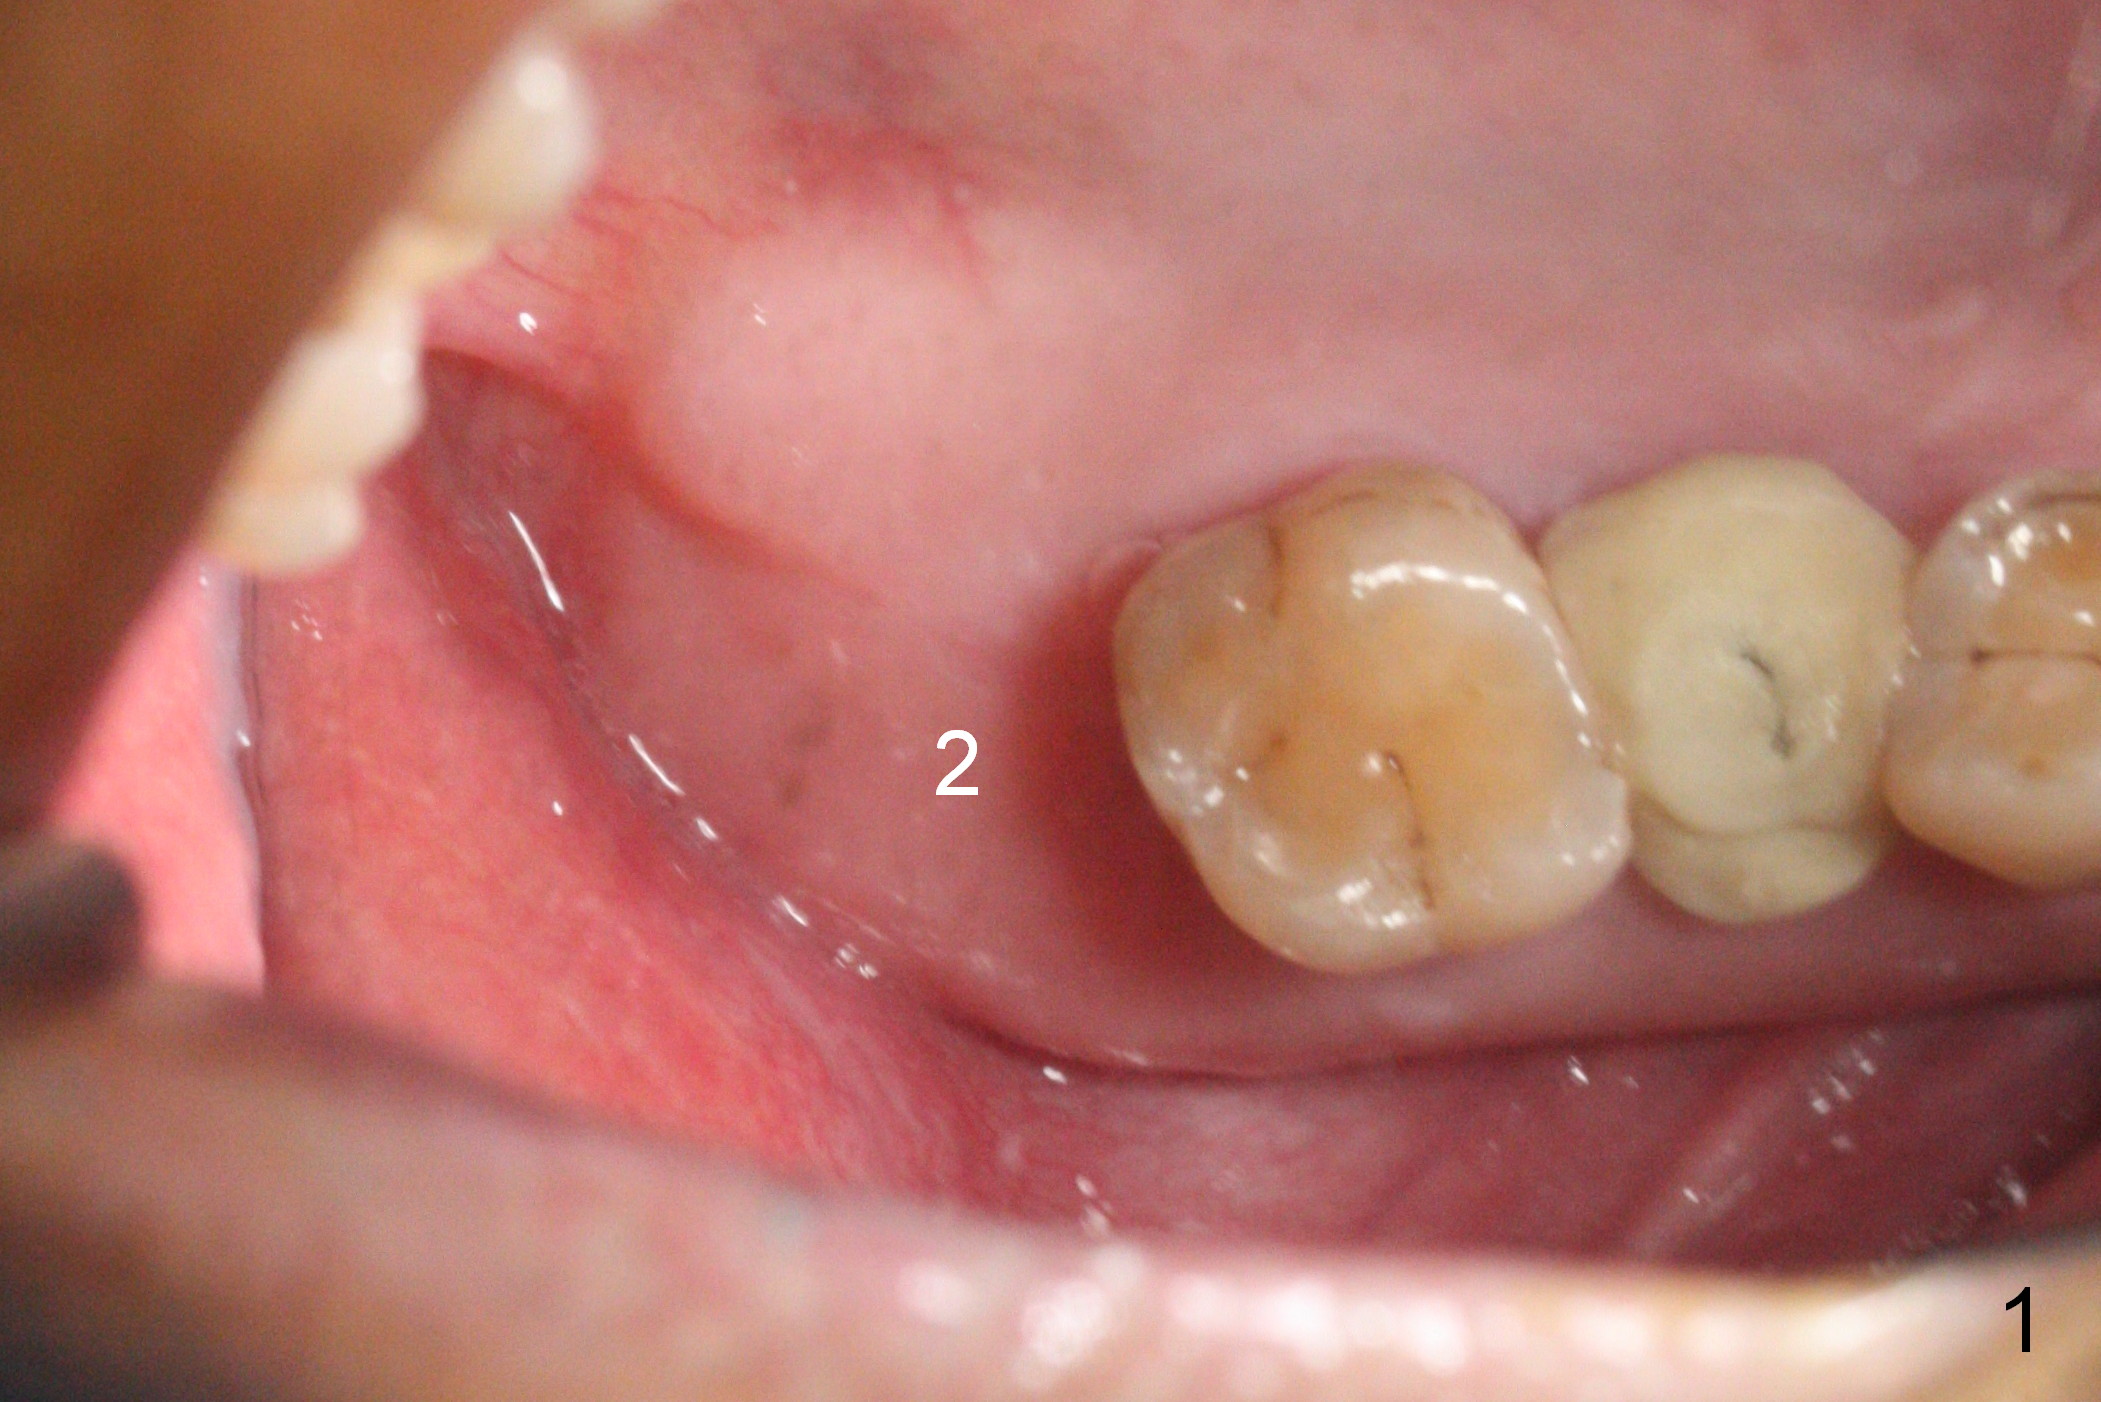

Since the ridge at the site of #2 is wide (Fig.1), Magic Split is used for access and bone density determination. In fact it enters for 9 mm (gingival level), followed by Magic Expander (ME) 3 mm (Fig.2 *). The center of the latter is 3.9 mm from the distal surface of the tooth #3. Lindamann bur is used to move the osteotomy distal, followed by sequential use of MEs until 4.3 mm one. When a 5x9 mm dummy implant is placed, its center is somewhat mesial (Fig.3 brown line). What needs to be done is change the trajectory to the red line so that the coronal end of the definitive implant (5.5x9 mm) will be placed evenly subcrestal (Fig.4,5). It is what happens, although slightly too subcrestal. Insertion torque is <35 Ncm; a 6x4 mm healing abutment is placed. ME 4.8 mm has to be tapped for 13 mm from gingival margin in order to let the implant penetrate the sinus floor. IBS implants seem to lack self tapping ability. Its tap drills should possess this capacity. Allograft/autogenous bone (harvested from dummy implant) is placed prior to implantation. The patient returns for impression 6 months postop (Fig.6,7; #4). A 5x4(3) mm abutment is placed; its height is reduced as well as the opposing supraerupted tooth (Fig.5) prior to impression.